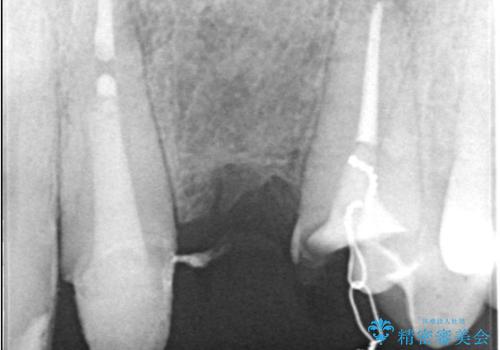

左上1番目~3番目にかけてブリッジの仮歯が入った状態で来院された患者さんで、左上3に縁下カリエスを認め抜歯してインプラントか牽引(エクストリュージョン)を行うか、歯肉根尖側移動術を行うか選択いただき牽引の後補綴処置を行うこととしました。

左上3の牽引を1か月半ほど行った後、補綴治療を行っています。

両支台歯とも根尖病巣は認められなかったため、ファイバ-コアからのやり替えとしました。